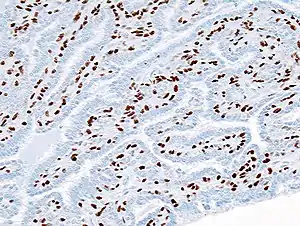

| Histopathology of intraductal papilloma of the breast by excisional biopsy. Immunostaining for p63 protein. | |